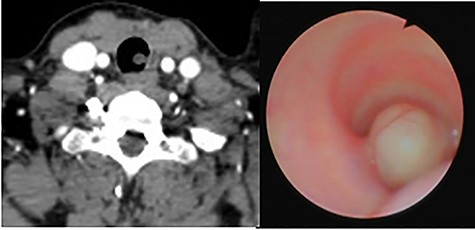

A non-smoker 31-year-old female with a history of Turner syndrome and Follicular thyroid carcinoma treated by total thyroidectomy and radical neck dissection, presented to her follow-up visit at the oncology department. The patient did not report symptoms such as dyspnea, cough, wheezing, or neck masses. No tumors or abnormal breath sounds were present during the physical examination. The follow-up computed tomography (CT) scan incidentally showed a partial airway obstruction secondary to a 14 mm endotracheal tumor (Fig. 1). There were no lymphadenopathy or mediastinal masses. Flexible bronchoscopy confirmed a 14 × 8 × 5 mm, smooth and oval-shaped tumor at the left posterior tracheal wall.

(A) CT scan showing an endotracheal tumor at the left posterior tracheal wall; (B) bronchoscopy view showing partial airway obstruction caused by the tumor.